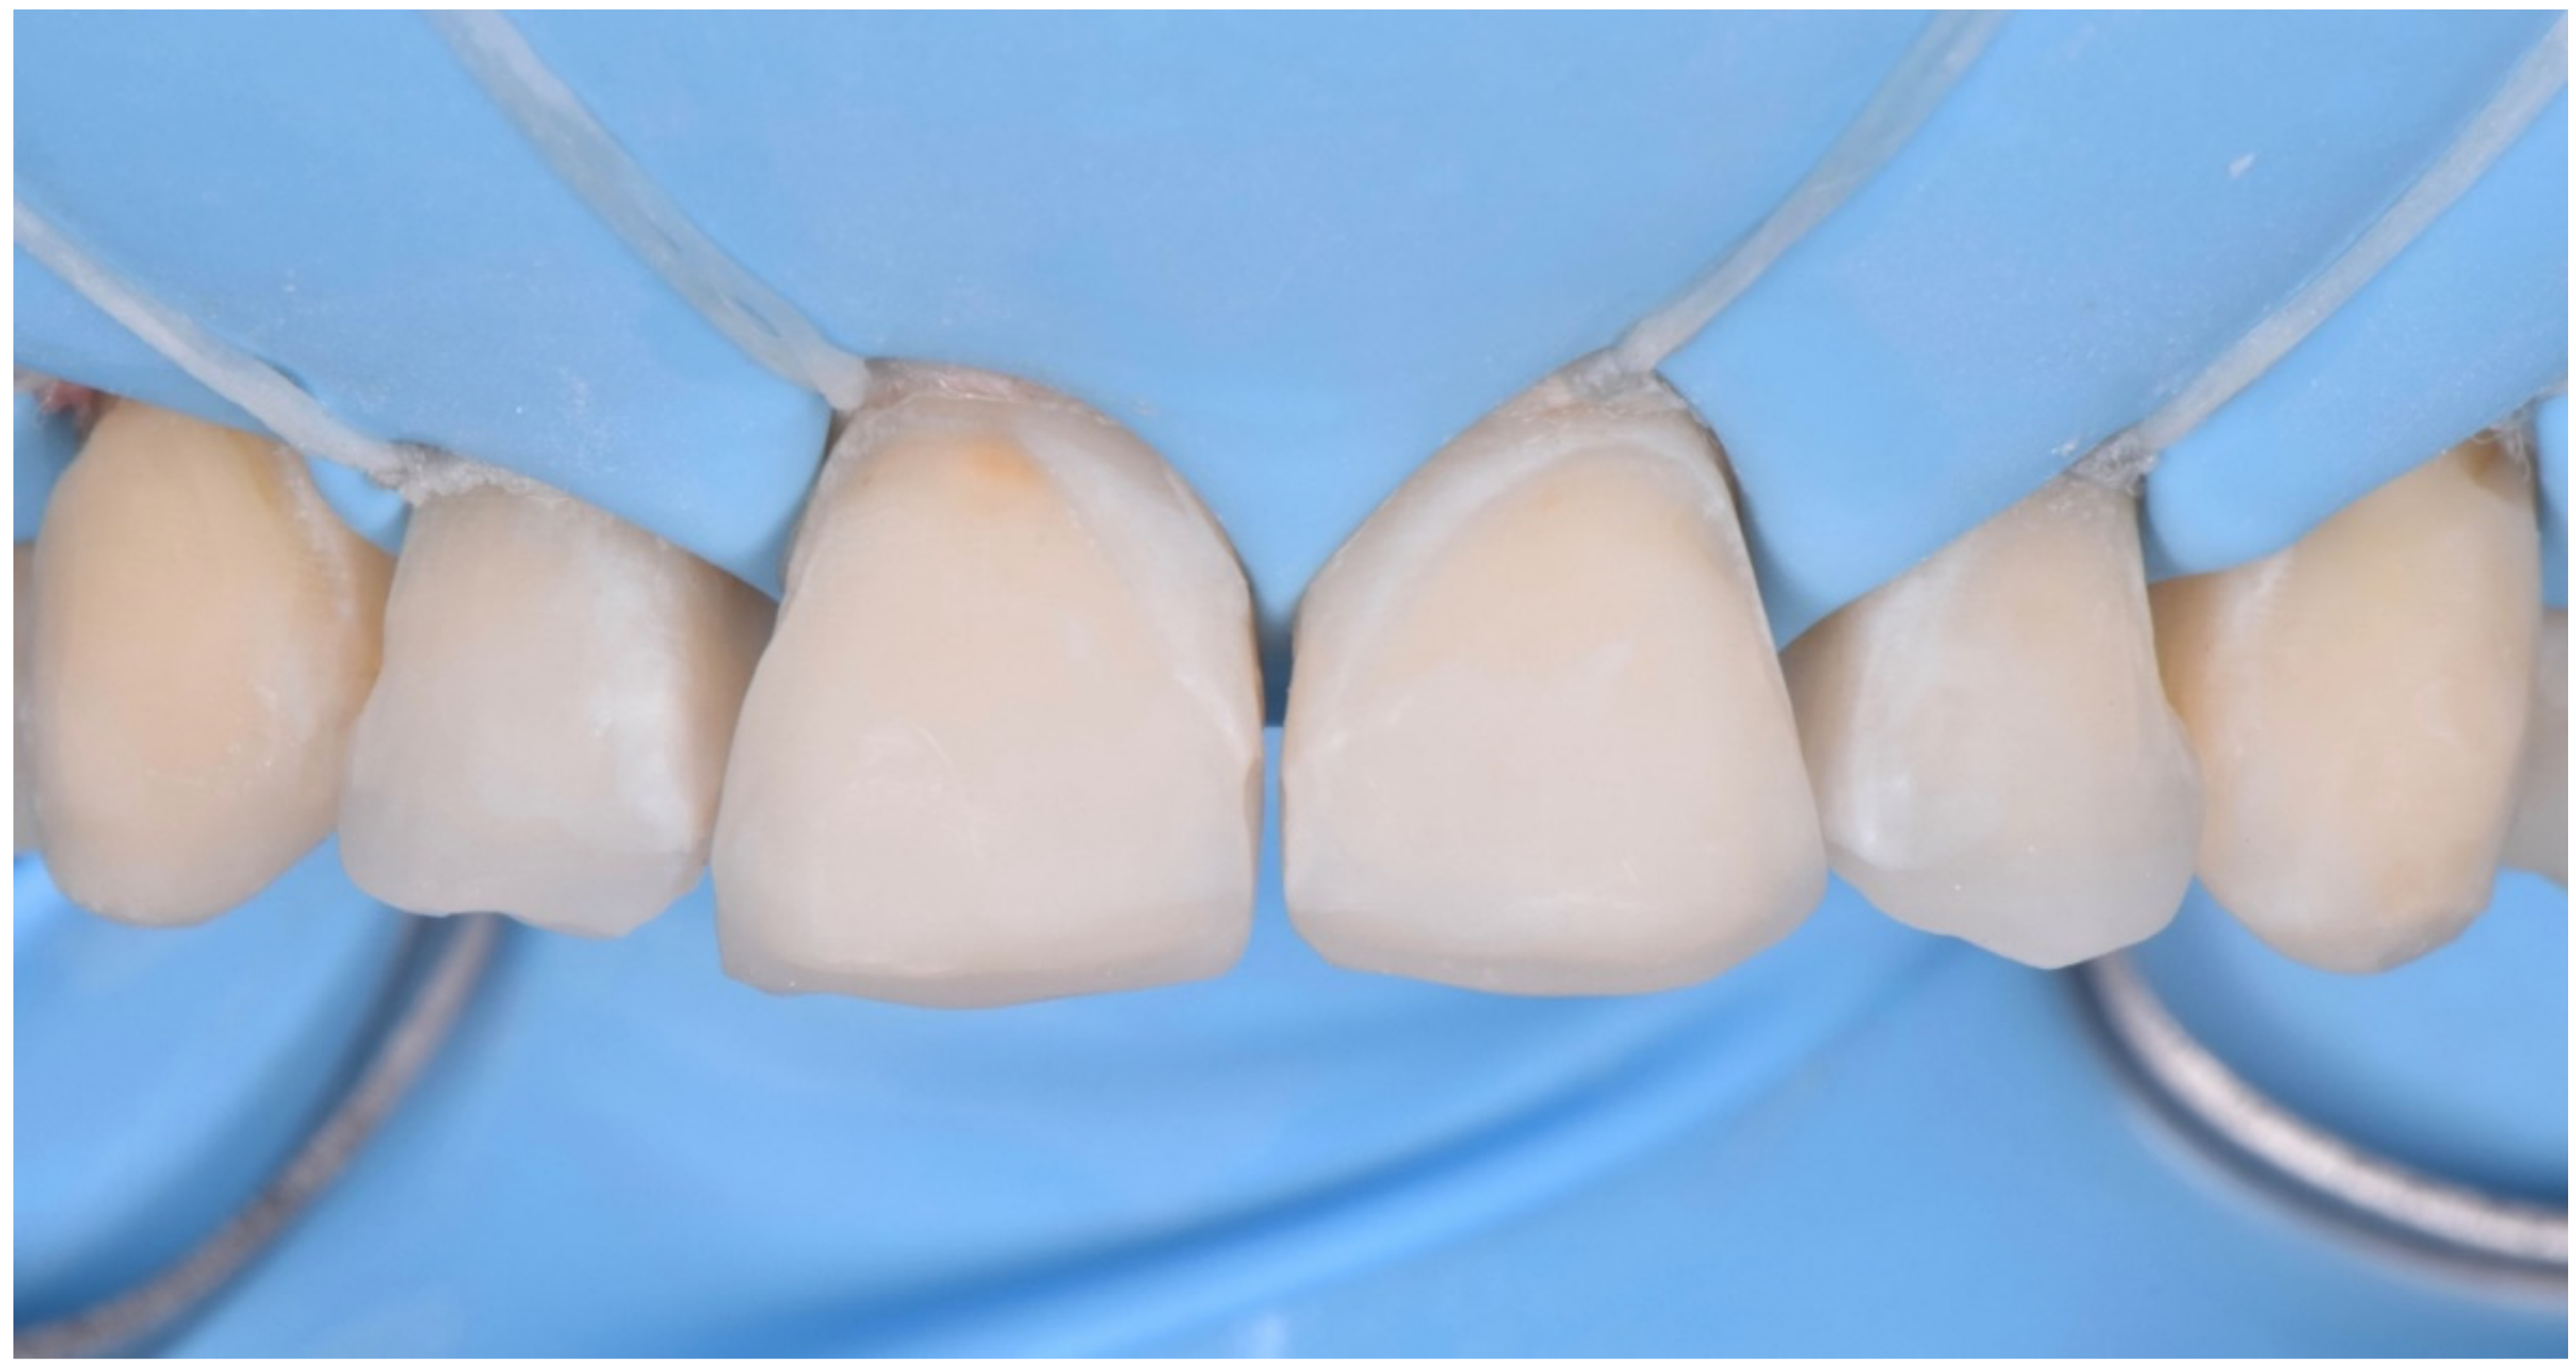

2.2. Restorative Phase